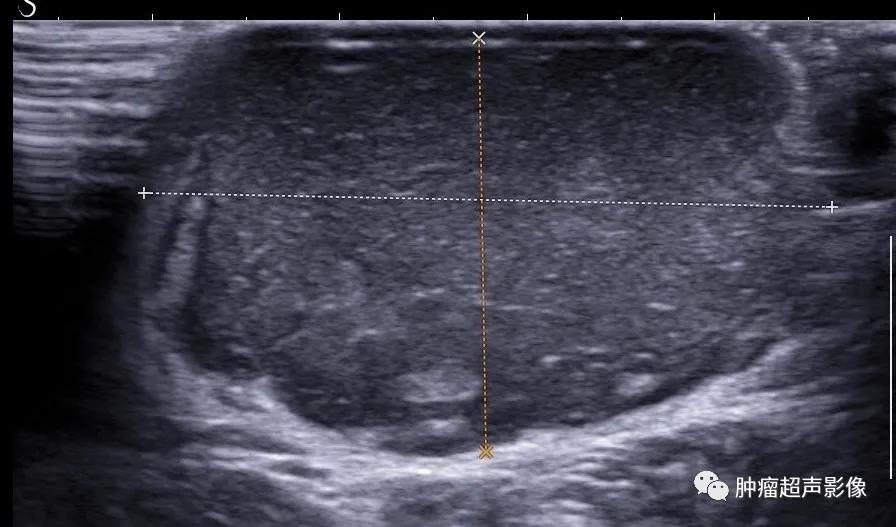

病理证实的隆突性皮肤纤维肉瘤:上臂隆起于皮肤表面的无痛肿块,呈紫红色,椭圆形,水平方向生长,内回声不均(见不规则条带状高回声),边缘可见伪足状低回声伸入高回声脂肪内,血流丰富。